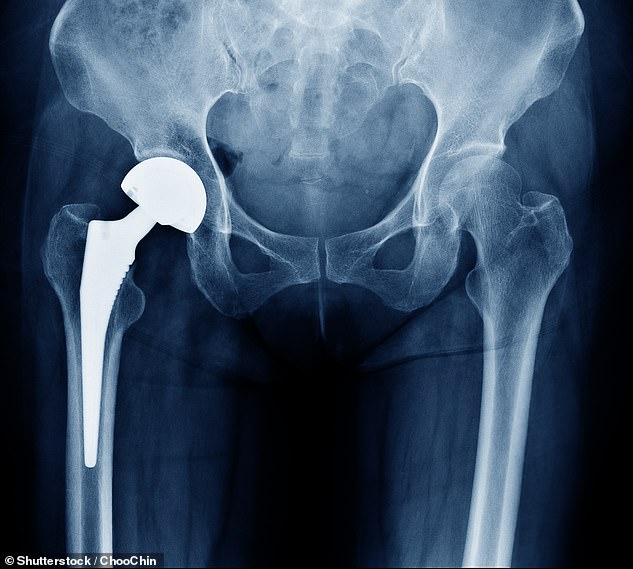

Ein Speichelabstrich vor Ihrem Hüftgelenkersatz könnte vorhersagen, ob das Verfahren funktioniert.

Etwa zehn Prozent der Briten werden sich im Laufe ihres Lebens einer Gelenkersatzoperation unterziehen. Das Verfahren wird häufig verwendet, um Schäden im Zusammenhang mit Arthritis oder altersbedingtem Verschleiß zu beheben.